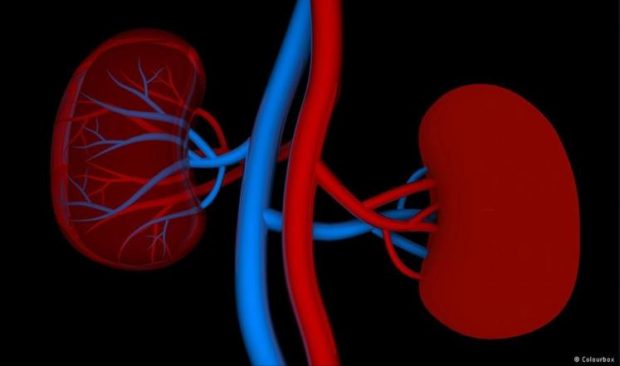

أفادت دراسة كندية حديثة بأن الولادة المبكرة (قبل إتمام 37 أسبوعا من الحمل) قد تؤدي إلى إصابة الطفل بارتفاع ضغط الدم في مرحلة البلوغ، بالإضافة إلى صغر حجم الكليتين.

ووجد الباحثون أن البالغين الذين ولدتهم أمهاتهم مبكرا كانت لديهم معدلات ضغط الدم أعلى بواقع خمس نقاط، مقارنة بأقرانهم الذين ولدوا في المعدلات الطبيعية، كما وجدوا أيضًا أن حجم الكليتين كان أصغر لدى المجموعة الأولى بالمقارنة بالمجموعة الثانية.